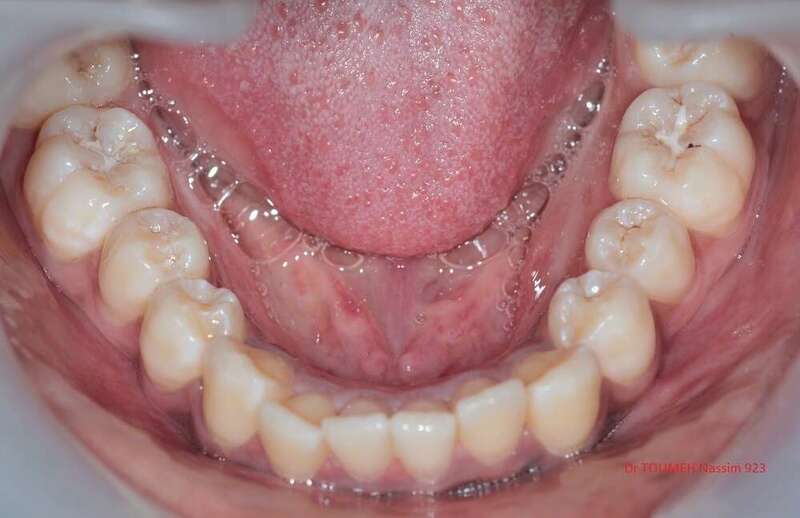

Latérales naines et orthodontie

la forme des dents influence grandement l’esthétique du sourire

La malformation des incisives latérales en est l'illustration

Le traitement consiste à redresser les dents à l'aide d'un appareil orthodontique (Multiattaches) et à redonner une forme normale aux dents malformées.

Dans ce cas présenté des couronnes provisoires en résines ont été posées.

Avant